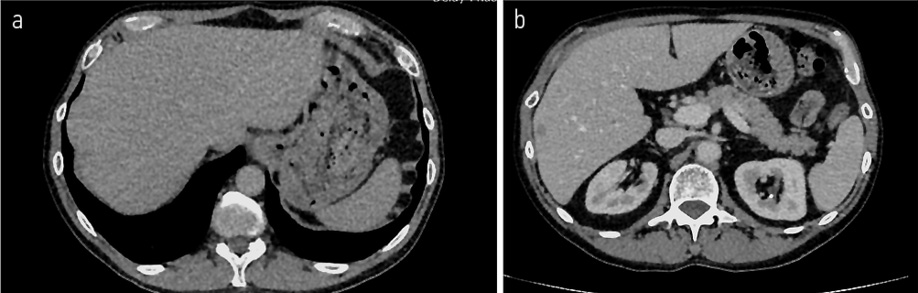

Рис. 8. МРТ ОМТ от 18.08.2022 в сравнении КТ ОМТ от 02.11.2022. Состояние после 3 курсов лекарственного лечения по схеме карбоплатин + иринотекан.

Fig. 8. Pelvic MRI dated 18.08.2022 in comparison with pelvic CT dated 02.11.2022. State after 3 courses of drug treatment with carboplatin + irinotecan.

С 08.2022 начал получать полихимиотерапию (ПХТ) по схеме: карбоплатин + иринотекан. По данным контрольного обследования 18.08.2022 отрицательная динамика в виде увеличения размеров метастатических очагов в костях таза, наибольшими размерами в левой подвздошной кости на уровне тазобедренного сустава до 25×23 мм (ранее до 17×15 мм), в крыле правой подвздошной кости до 36×18 мм (ранее до 15×7 мм), в боковой массе крестца слева до 24×26 мм (ранее до 18×14 мм); рис. 8. Обсужден на консилиуме №91016 от 09.11.2022, рекомендовано: проведение паллиативной лучевой терапии последовательно на область правой и левой половины таза в разовой очаговой дозе (РОД) 6,5 Гр до суммарной очаговой дозы (СОД) 26 Гр.

С 08.2022 по 22.12.2022 проведено 6 курсов лекарственного лечения по схеме карбоплатин + иринотекан. По результатам контрольного обследования от 01.2023: отрицательная динамика в виде увеличения размера очагов в костях скелета: в левой подвздошной кости до 29×25 мм (ранее до 25×23 мм) и 38×26 мм (ранее до 33×25 мм), в крыле подвздошной кости до 56×19 мм (ранее 27×22 мм), в боковой массе крестца слева до 28×23 мм (ранее 27×22 мм) и появления новых мелких очагов в бедренных костях до 5 мм и в телах LII–IV позвонков диаметром до 3 мм; билобарного очагового поражения печени: в S2 – до 20×23 см, на границе S2|3 – до 13×15 см, в S6 – 8×11 мм (рис. 9, 10).